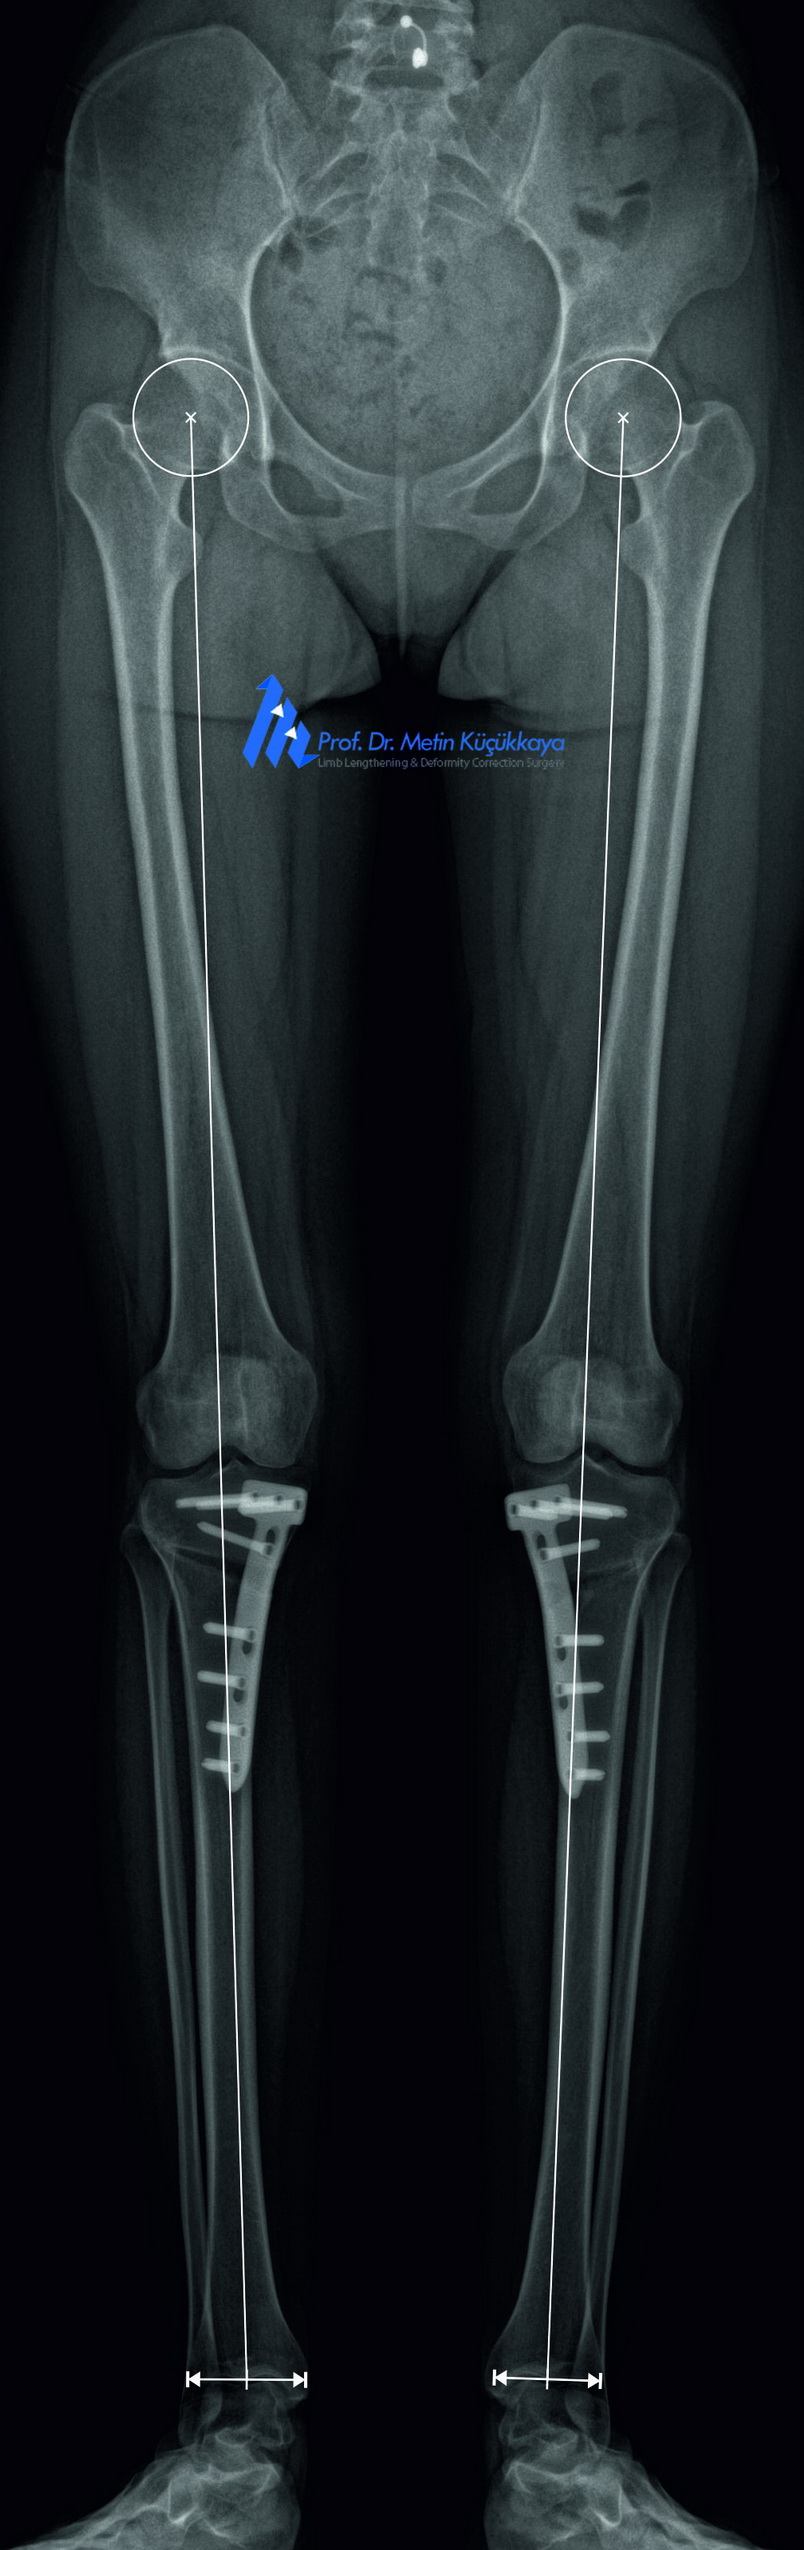

Preoperative calibrated EOS images with CorelDRAW®-based measurements (left) and planning (middle), followed by postoperative X-rays (right) showing successful correction.

📐 Preoperative Planning:

The patient underwent long-standing calibrated EOS imaging. Precice planning performed using with CorelDRAW®, mechanical axis deviation, rotation, and implant positioning were carefully analyzed. The plan involved simultaneous correction of both alignment and hardware-related complications.

✅ Postoperative Course and Outcome:

Radiographs confirmed anatomical correction and implant stability. Wound healing was achieved, and the patient gradually returned to independent ambulation.